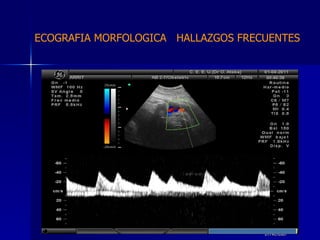

DTFRC-2007 ECOGRAFIA MORFOLOGICA  HALLAZGOS FRECUENTES   MATERIAL Y METODO ES UN ESTUDIO DESCRIPTIVO, RETROSPECTIVO  DE ESTUDIO ECOGRA FICOS REALIZADOS ENTRE MARZO 07 A MARZO 08 EQUIPO DE ALTA RESOLUCION   VOLUSON 730 PRO  MEDISON SA 8000 live MEDISON SA 8000SE CRITERIO DE INCLUSION:   POBLACION GENERAL    GESTACIONES  20 a 24 SEMANAS   UNIVERSO  N 211

DTFRC-2007 ECOGRAFIA MORFOLOGICA  HALLAZGOS FRECUENTES   Sistema Nervioso Central  8  Cardiovascular  0 Genitourinario  6 Musculos Esqueleticos  2 Gastrointestinales  2  Otros  12  Total  30   NUMEROS DE ANOMALIAS POR SISTEMA n N  211